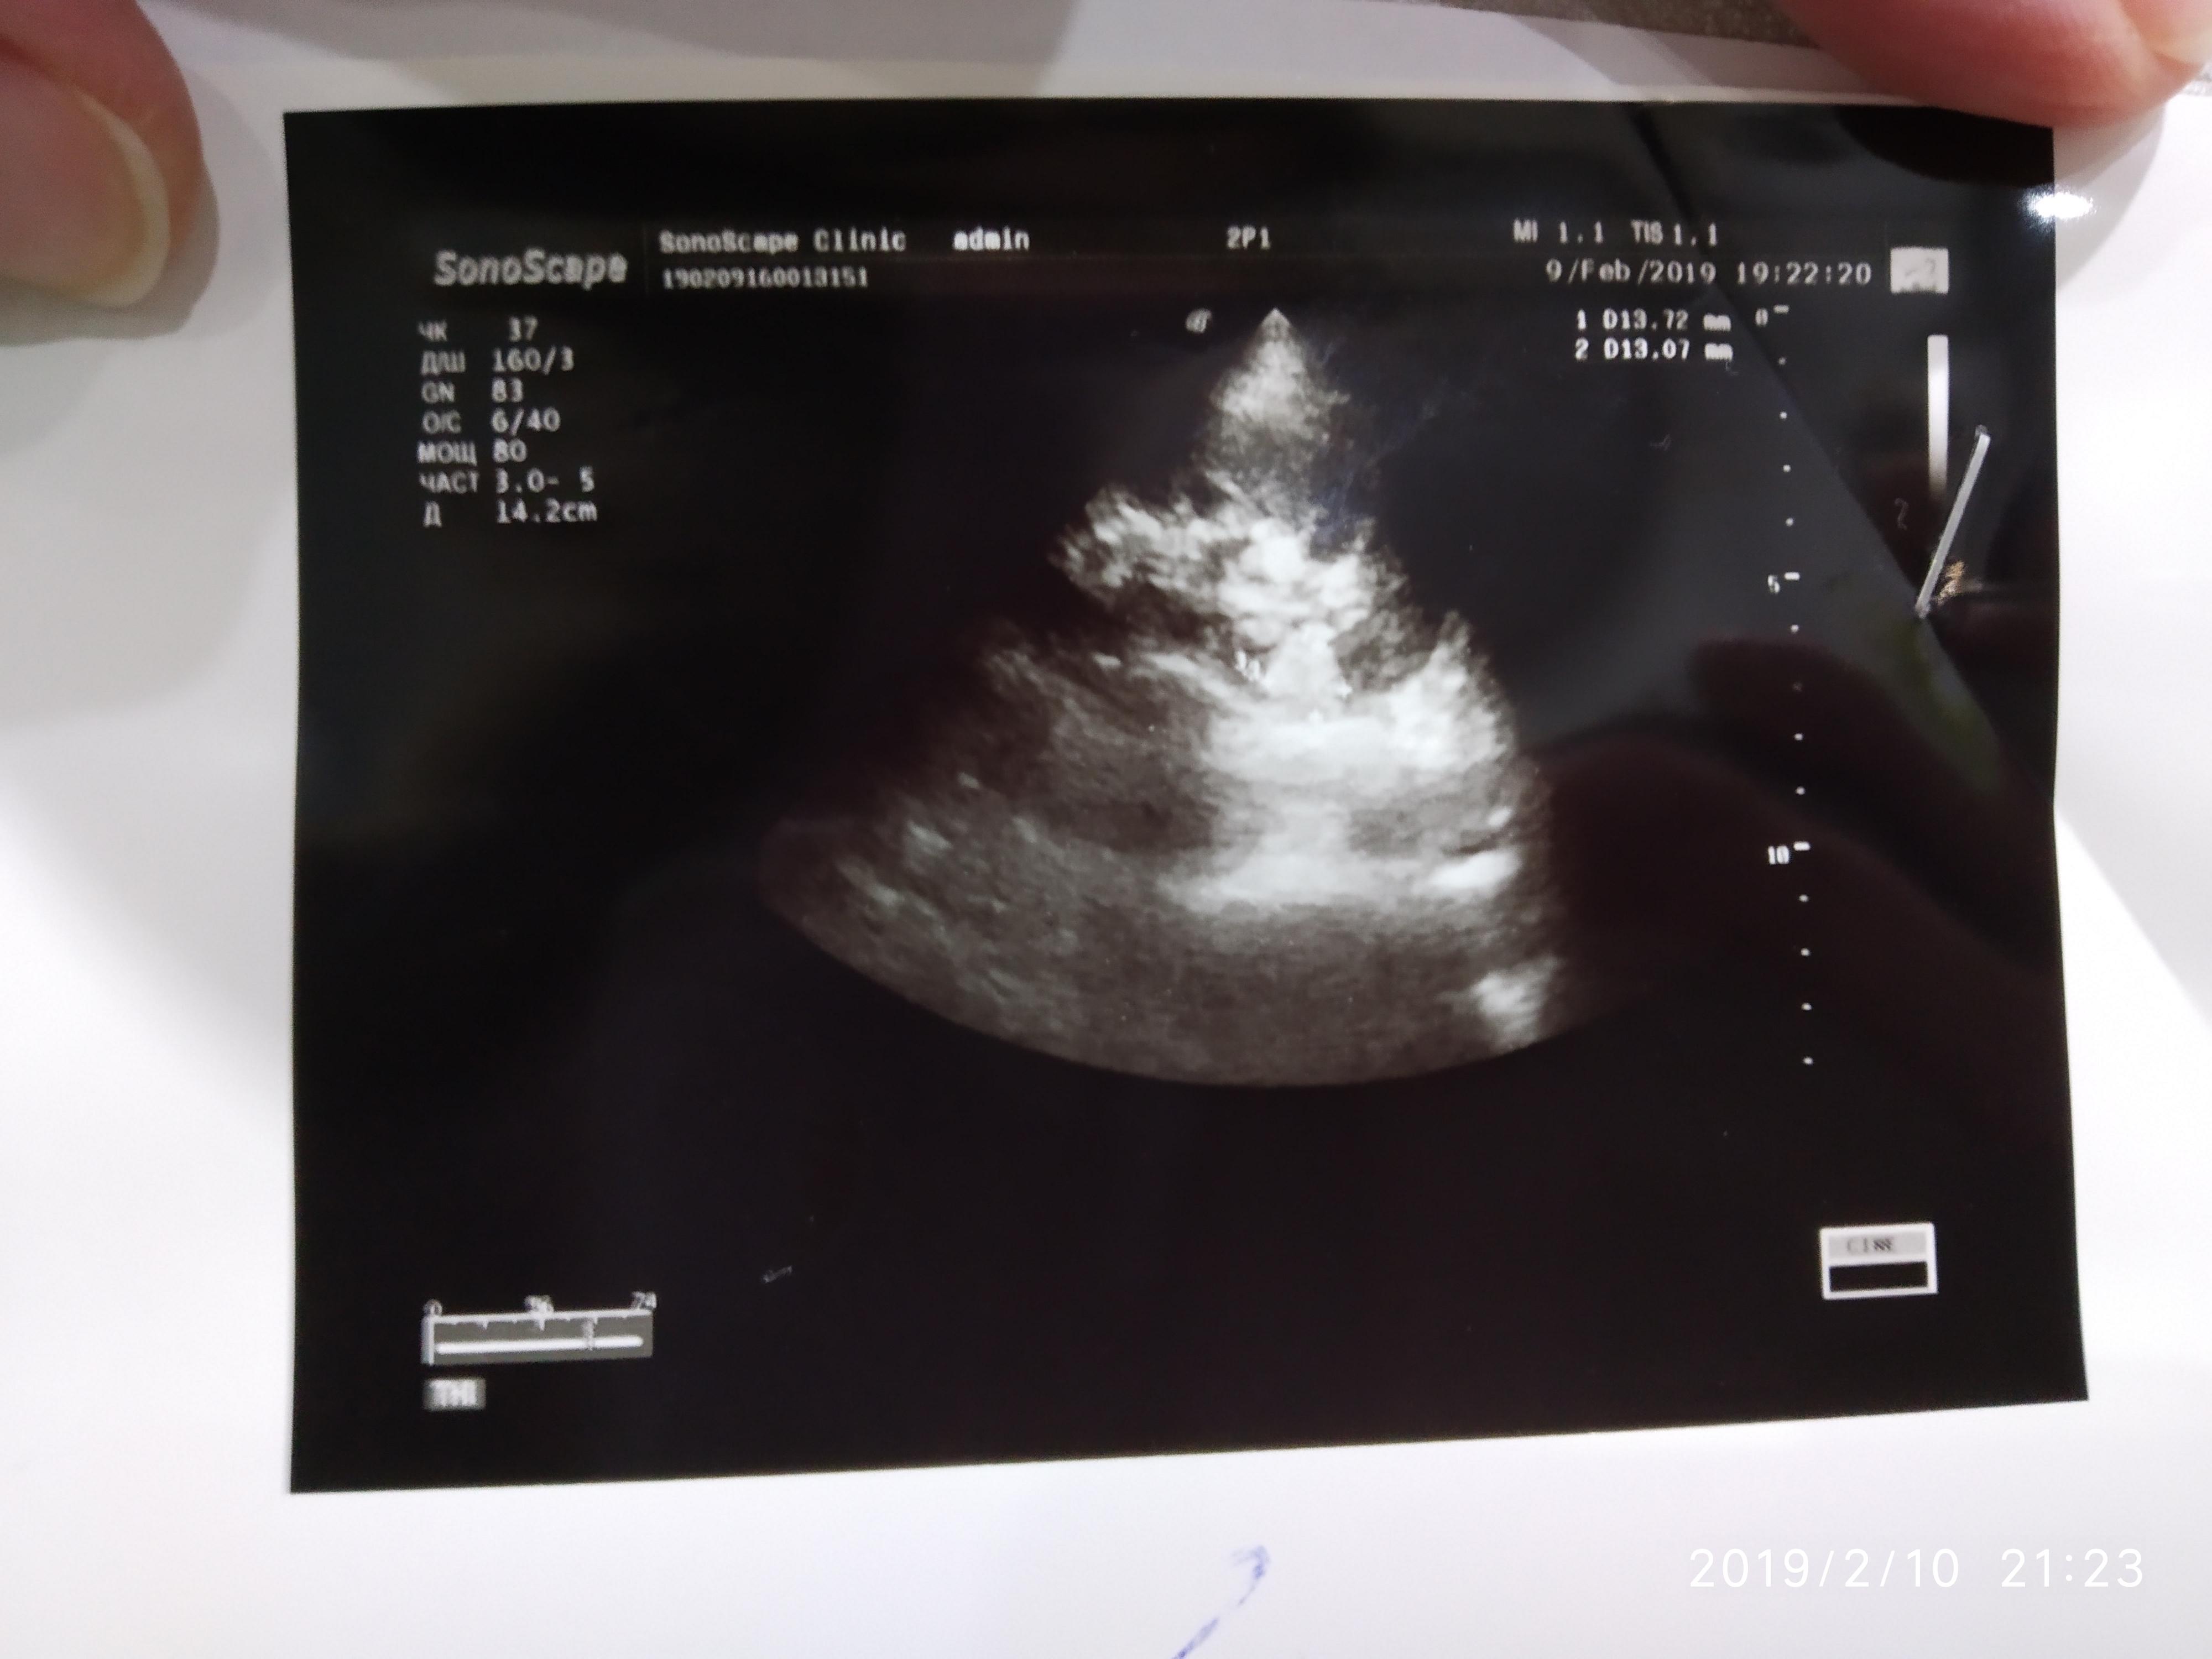

Здравствуйте. Кардиолог направил на УЗИ почек и надпочечников (иногда повышение АД и постоянно высокий пульс). У нас в городе нет врача уролога. Поеду в областной центр как только смогу записаться на приём врача. Помогите расшифровать результаты УЗИ. Я почитала что можно носить бандаж, чтобы удерживать почку на месте. Можно ли мне в моей ситуации носить бандаж? И про левую почку врач УЗИ сказала про какие-то сосуды, сказала просто повторно пройти обследование через полгода, а в результате читаю липома? Спасибо.

Здравствуйте! Надо сделать МСКТ( мультиспиральная компьютераня томография) почек, мочеточников. А потом наблюдать уже можно - УЗИ. По поводу нефроптоза - бандаж носить можно. И укреплять мышцы передней брюшной стенки. Удачи!